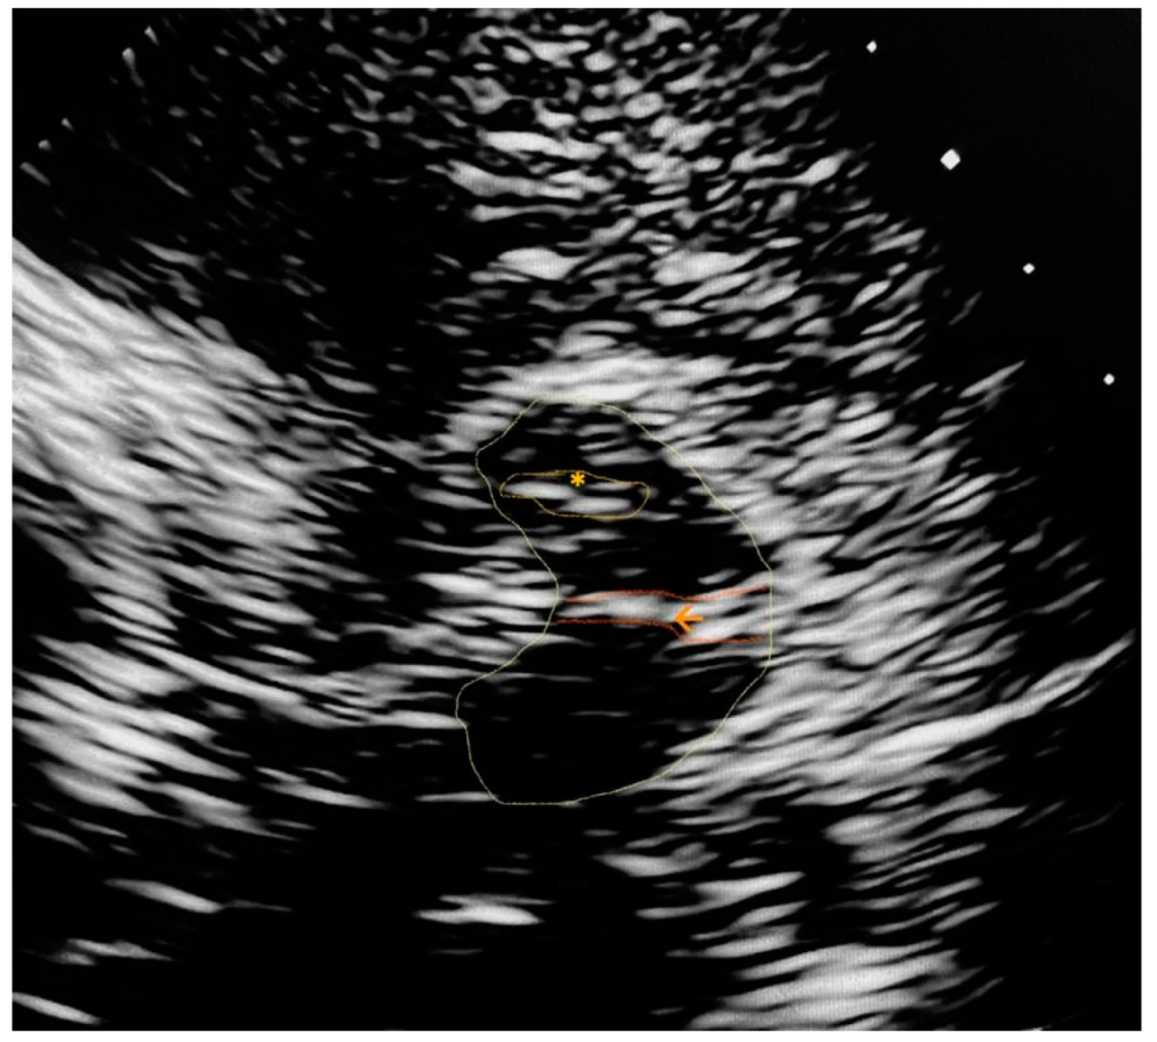

Appendix A. Trascranial Ultrasound Images Identifying the Main Referred Structures